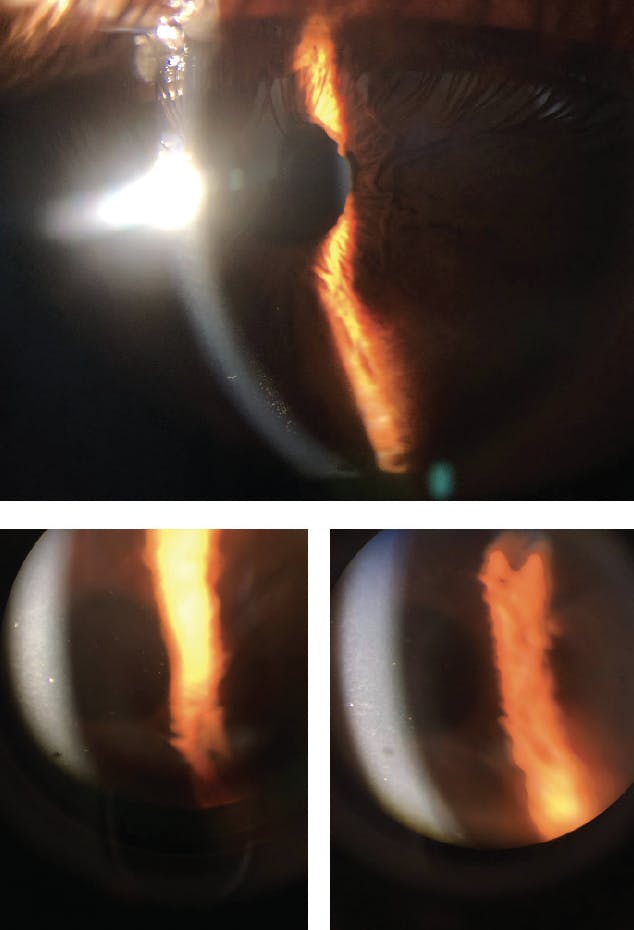

Anterior chamber reaction ranged from rare cells to 2+ cells. Interestingly, in all patients, anterior chamber reaction was accompanied by pigmented cells and flare that resembled a pigment storm in the anterior chamber. Fine pigmented keratic precipitates and pigment dusting on the corneal endothelium were also identified (Figure 1). Mydriasis with sectoral iris atrophy, specific for ischemic vasculitis in viral uveitis, was detected in two patients, one of whom exhibited these symptoms bilaterally (Figure 2).

Figure 1. The appearance of fine pigmented keratic precipitates and pigment dusting on the corneal endothelium.

Figure 2. The biomicroscopic appearance of mydriasis in the right (A) and left (B) eyes of a patient with uveitis related to COVID-19. The bilateral presentation of mydriasis in the same patient (C).